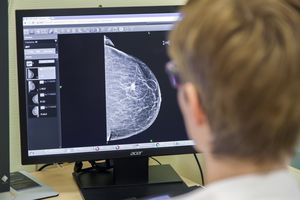

In der Mehrzahl der Fälle entstehen Tumore in den Milchgängen der Brust (duktal). Diese Tumore treten oft als „Knoten“ in Erscheinung. Vergleichsweise selten geschieht dies in den Drüsenläppchen (lobulär). Diese wachsen häufiger diffus und sind daher schwieriger zu erkennen.

Solange eine duktale Zellveränderung die Basalmembran (Grenzmembran) nicht überschritten hat, handelt es sich um ein duktales Carcinoma in situ (DCIS), eine Vorstufe von Krebs, die keine Tochtergeschwülste bildet und daher für das Leben ungefährlich ist. Sie wächst jedoch oft unbemerkt und kann daher sehr groß werden. Aus diesen Krebsvorstufen kann jederzeit ein Brustkrebs entstehen. Sie müssen daher sicher aus der Brust entfernt werden.